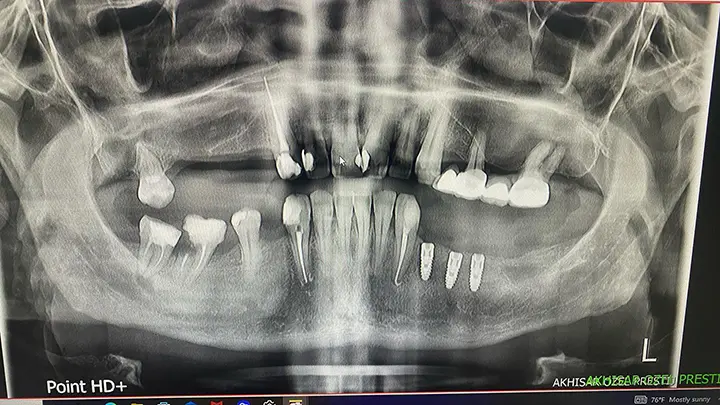

DVT Dental Tomografi Çekimi